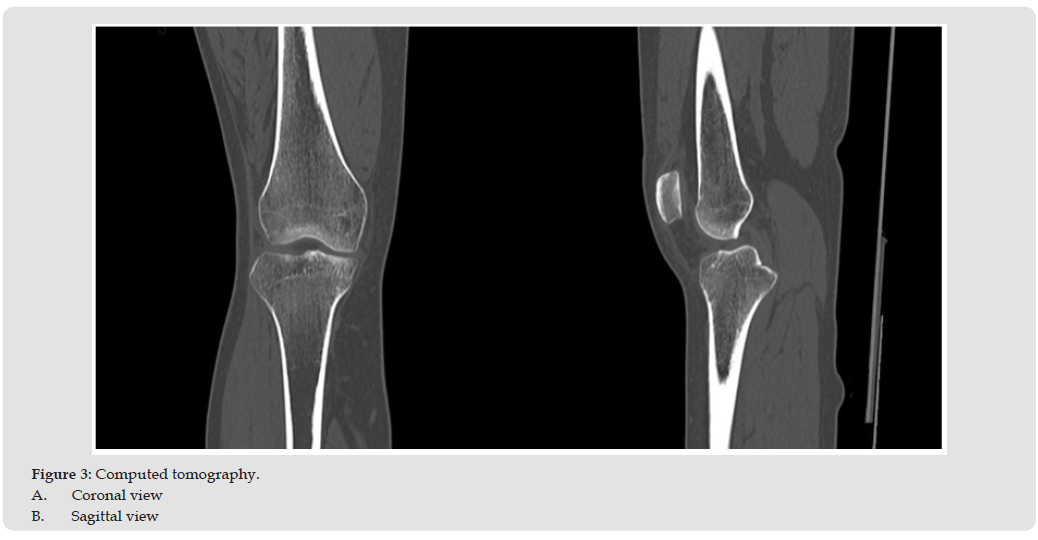

A 28-year-old female presented with severe right knee pain and gait disturbance. The symptoms began after a dog bumped her. She nearly fell, stepped forward with her right foot to brace herself, during which her knee gave way. She was taken to a nearby hospital where MRI revealed no significant findings (Figure 1). She returned to work, but her knee pain gradually worsened. One month later, a repeat MRI showed a bone bruise in the anterior tibial plateau (Figure 2). Her symptoms persisted for approximately 2 months. Therefore, prompting referral to our department. Her past medical and family histories were unremarkable. Physical examination revealed no swelling, or effusion, but tenderness was noted in the right knee. The range of motion was 0°-145°. McMurray test for meniscal injury were negative. The anterior and posterior drawer tests, as well as varus and valgus stress tests, were normal. The Lachman test was positive. The patient had no patellofemoral symptoms. Her Lysholm knee score was 42. Plane radiographs showed no bony or soft tissue abnormalities, including intra-articular loose bodies. Computed tomography revealed no subchondral bone loss (Figure 3). MRI confirmed the presence of a bone bruise in the anterior tibial plateau.